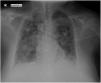

A 56-year-old woman was admitted to the Intensive Care Unit due to urological septic shock and hypoxemic respiratory failure. The chest X-ray revealed bilateral pulmonary infiltrates with an alveolar pattern, and the patient was diagnosed with adult respiratory distress syndrome (Fig. 1).